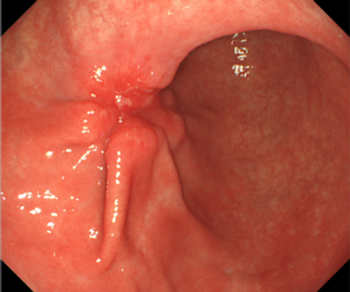

The use of a noninvasive colorectal cancer screening test called a multi-target stool DNA test (mt-sDNA) detected the disease in patients who had previously avoided more invasive screening procedures.